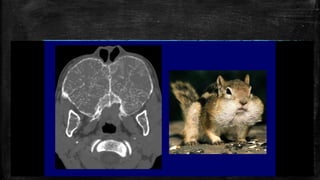

Salt and pepper sign –jugular

paraganglioma

• #77 Salt and pepper sign. FLAIR axial MRI image of the left temporal bone shows an isointense mass (arrows) in the region of the jugular foramen. The mass is heterogeneous, with dark and slightly bright areas within it. Axial CT scan (B) in the same patient shows the mass causing destruction of the surrounding bone (arrows). An external carotid angiogram (C) shows tumor blush (black arrow) due to hypervascularity. These findings are suggestive of a glomus jugulare tumor of the jugular foramen

• #78 Salt and pepper” sign of paraganglioma. (a) Axial non-contrast enhanced T1-weighted image demonstrates a circumscribed mass (white arrowhead) splaying the internal and external carotid arteries and demonstrating a speckled appearance with foci of intrinsic bright T1 signal (white open arrows). (b) Axial T2-weighted imaging shows the mass (white arrowhead) to have areas of peripheral dark T2 signal (white solid arrows). (c) This pattern has been likened to the appearance of “salt and pepper” and is pathognomonic for paraganglioma.